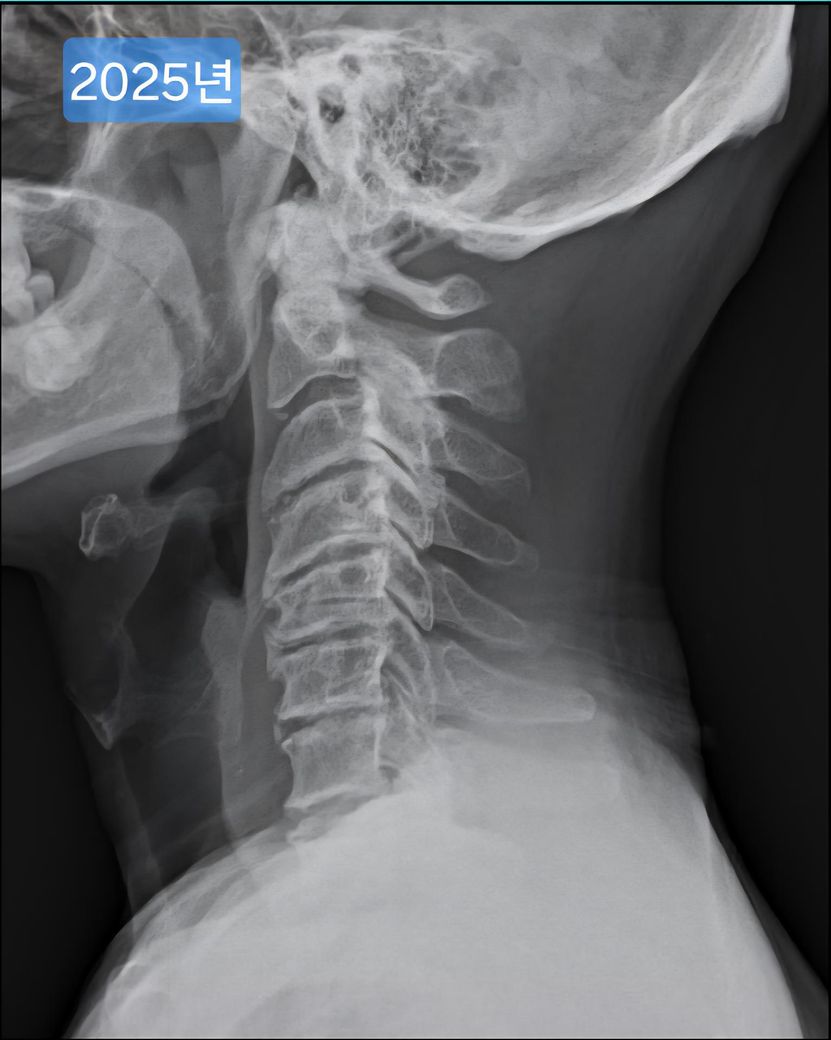

일자목, 경추사이 공간이 좁은 안좋은 형태의 목상태 입니다